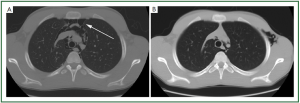

In December 2010, a 16 years-old man was admitted to a local hospital for complaints of chest pain, dyspnea, and neck pain presenting after spasm coughing. His medical history was unremarkable. Chest X-Ray and CT scan diagnosed the presence of pneumomediastinum without signs of pneumothorax and/or pleural effusion (Figure 1A). Thus, the patient was transferred to our hospital for diagnosis and treatment. Bronchosopic was attempted, but no endotracheal lesions were found. Gastrografin swallow excluded any esophageal perforation. Thus, the diagnosis of SPM was made. Medical treatment was done (reassurance, bed rest, oxygen, analgesic, and antibiotic therapy) with gradual improvement of clinical condition. Chest CT scan performed after 9 days, showed the complete disappearance of pneumomediastinum with no evidence of bullae (Figure 1B).

Figure 1. Massive emphysema of the superior mediastinum, around the trachea and vessels (A). Complete disappearence of pneumomediastinum (B).